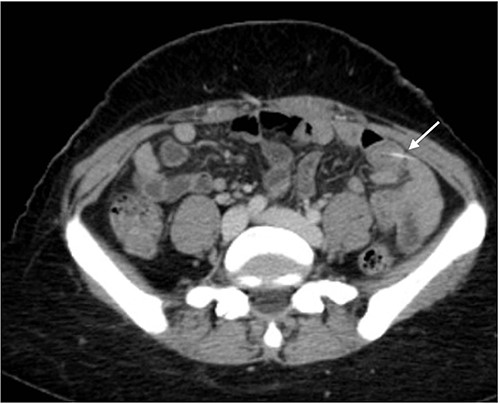

The abdominal exam showed severe tenderness in LLQ + rebound tenderness. The white blood cell count was 9000/mm3. Contrast-enhanced CT of the abdomen (Figs 1 and 2) showed a transversely oriented linear hyperdense FB structure seen within the ilea loops in the LLQ measuring ~2 mm in thickness and 18 mm in length traversing the bowel wall, which demonstrates localized mural wall edema with minimal surrounding fatty haziness; however, there was no adjacent extra-luminal air or localized collections, and right adnexal cyst.

Axial views of contrast-enhanced CT of the abdomen showed a transversely oriented linear hyperdense FB (arrow) structure seen within the ilea loops in the lower quadrant.